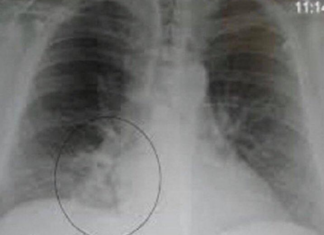

OVA SMJESA JAČA IMUNITET, LIJEČI PLUĆA, DJELUJE PROTIVUPALNO: Trebaju Vam SAMO 3 SASTOJKA

U današnjem članku pišemo o napitku koji može ojačati vaš imunitet i poboljšati zdravlje pluća. Svi tražimo prirodne načine kako da očuvamo zdravlje, a ovaj jednostavan napitak može biti pravi saveznik u tome. U svijetu u kojem su virusi i prehlade na svakom koraku, održavanje snažnog imuniteta postaje ključ za prevenciju bolesti. Jedan od najučinkovitijih […]